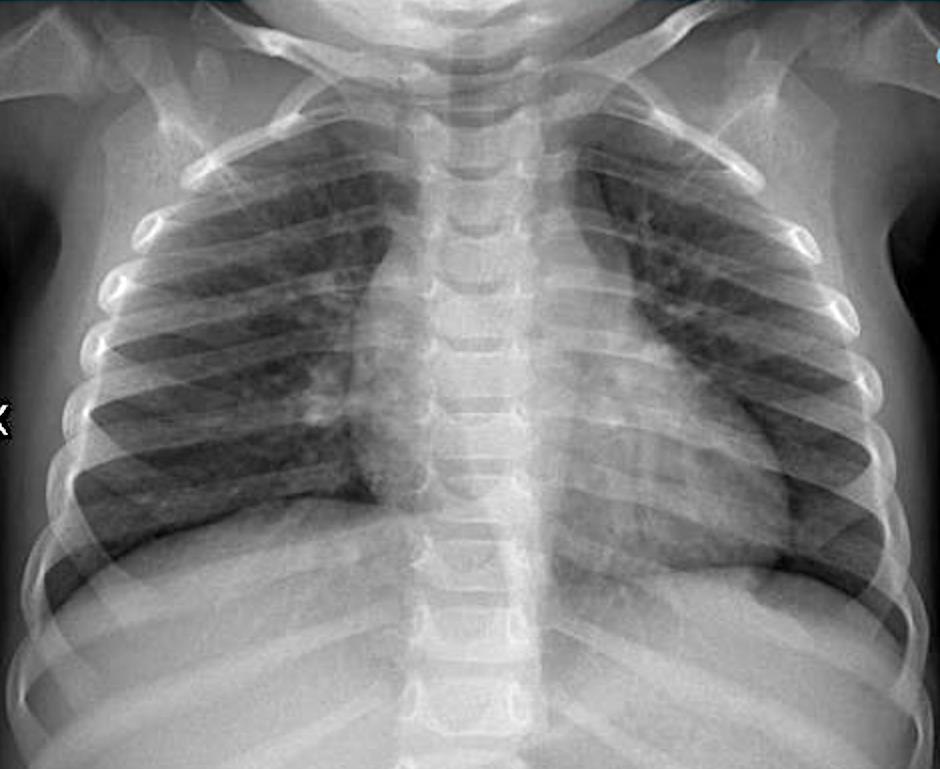

Imaging of Covid 19 infection in children CXR 8 38% 3% 51% 8%

Consolidation 35%

Collapse 3%

PeriBronchial thickening

51%

Hyperexpansion 7%

Effusion 4%

Imaging of Covid 19 infection in children CXR 9 C O V I D

Birmingham